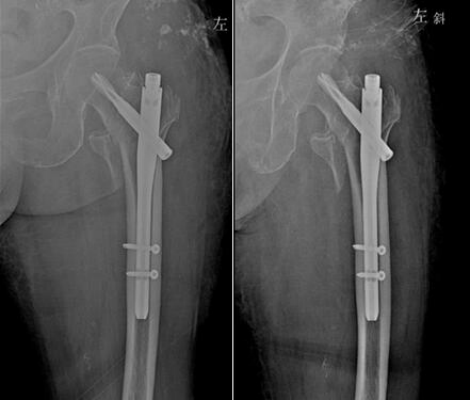

2. 髓内钉

髓内钉内固定可以使应力更均匀地分布于内植物与骨之间,其接近骨骼轴线,能更好地对抗弯曲应力[17]。髓内钉固定骨质疏松性骨折,可以使患者早期负重,同时还更好地保护骨折周围软组织。髓内钉内固定最薄弱的区域是置入交锁钉的干骺端[18]。这个区域的髓腔较宽,主钉与皮质不接触,因此结构的稳定性依赖于螺钉-主钉界面[19]。当选用髓内钉治疗骨质疏松性骨折时,应重点关注此区域,因为骨质量差会影响交锁螺钉的稳定。

随着髓内钉的不断更新迭代,设计和手术技术的双重提高,髓内钉治疗骨质疏松性骨折的适应症也逐渐扩大。例如:多平面交锁固定有助于提高骨折的稳定性,降低畸形愈合的风险[20];交锁螺钉替换为螺旋刀片,能增加应力负荷承载面积,将应力分散至更多的骨组织上,从而减少作用于髓内钉结构的应力[21];具有角度固定的交锁螺钉,可以通过减少交锁螺钉的摆动,实现更坚强的内固定[22]。轴向应力负荷的作用下,螺旋刀片的刚度比交锁螺钉增加41%,强度增加20%[23]。虽然,生物力学研究证实了以上新设计髓内钉的有效性,但是这些研究均为轴向应力负荷下的稳定性,还需进一步研究在扭转应力和人体正常生理负荷下的稳定性。